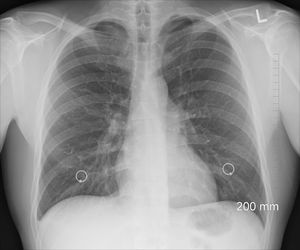

Lungenröntgen: Fibrose verhärtet das Gewebe (Foto: pixabay.com, oracast) |